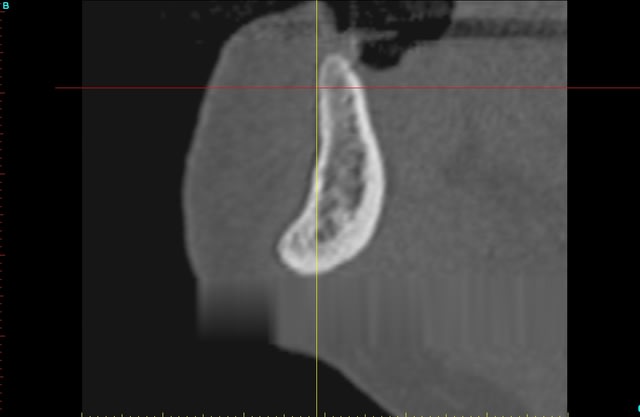

ce que je considère comme pas simple du tout expansion symphise.

ce fut long (pas loin de trois heures) mais bon!

3 h car je laisse l'os travailler , il faut qu'il "s'ecarte" lentement sinon craque.

pas du D1, sans fenetre laterale ça ne marcherais pas, par contre fin.